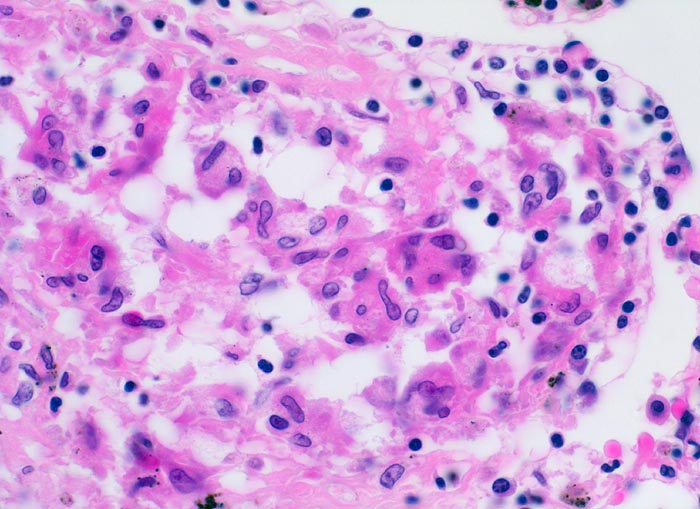

Die Morphologie der Erkrankung ist stadienabhängig. Initial findet sich eine lymphozytenreiche Alveolitis mit wenigen kleinen Granulomen. Die Granulome bestehen aus Aggregaten epitheloider Histiozyten teilweise mit Beteiligung von mehrkernigen Riesenzellen. Im Verlauf entwickeln sich zellreiche Granulome entlang der bronchovaskulären Bündel und der Interalveolarsepten, welche später konfluieren und vernarben. Die Riesenzellen können Asteroidkörperchen (sternförmige Kristalle) oder Schaumannkörperchen (lamelläre Verkalkungen) enthalten. Ein Teil der Patienten entwickelt eine irreversible Lungenfibrose.

• Zahlreiche produktive, nicht nekrotisierende Granulome aus dickleibigen Epitheloidzellen, Riesenzellen vom Langhanstyp und Lymphozyten.

• Bevorzugte Lokalisation der Granulome im Bereich von Bronchiolen und Pulmonalarterienästen. Das sollte der Kliniker dem Pathologen mitteilen: